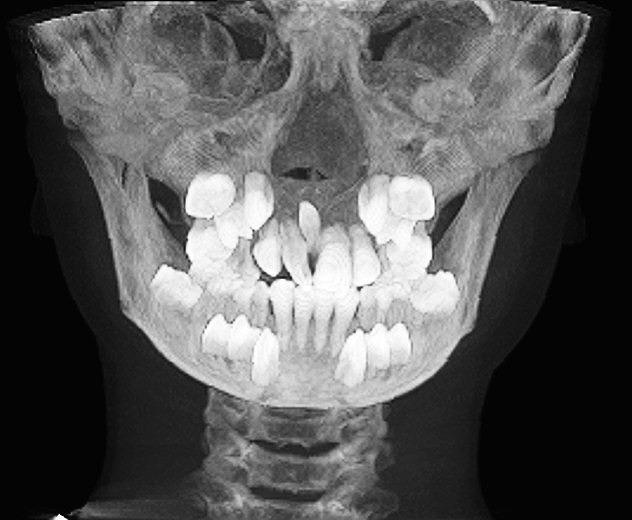

右の歯が90度回転して萌出してきています お母さんより心配になって来院|お知らせ |広島市安佐南区の歯科医院 右の歯が90度回転して萌出してきています お母さんより心配になって来院 トップ お知らせ・ブログ お知らせ 右の歯が90度回転して萌出してきています お母さんより心配になって来院 右の歯が90度回転して萌出してきています お母さんより心配になって来院 回転の度合いもひどいです 原因を探ります 逆性の過剰歯が存在 このように大きく逆向きに存在しています 骨の中央で抜きにくそうです 抜歯しました 縫合して終了となります この湯女歯が存在していました 抜糸時になります Web診療予約 初めての方へ 選ばれ続ける理由 院内設備について 歯が痛いしみる一般歯科 歯がぐらぐらする歯周病 健康な歯を保ちたい予防歯科 子供の虫歯予防をしたい小児歯科 銀歯をセラミックに審美歯科 白い歯を目指しませんか?ホワイトニング 矯正専門医がいるので安心矯正歯科 抜けた歯を補いたいインプラント・入れ歯 医院案内 スタッフ紹介 メリィハウス歯科クリニックオフィシャルホームページ ラベンダー歯科クリニックオフィシャルホームページ お知らせ・ブログ ホーム 診療科目 一般歯科 歯周病治療 予防治療 小児歯科 審美治療 ホワイトニング 矯正歯科 入れ歯・インプラント マウスピース矯正 初めての方へ 院長・スタッフ 設備紹介 医院案内・アクセス メニューを閉じる